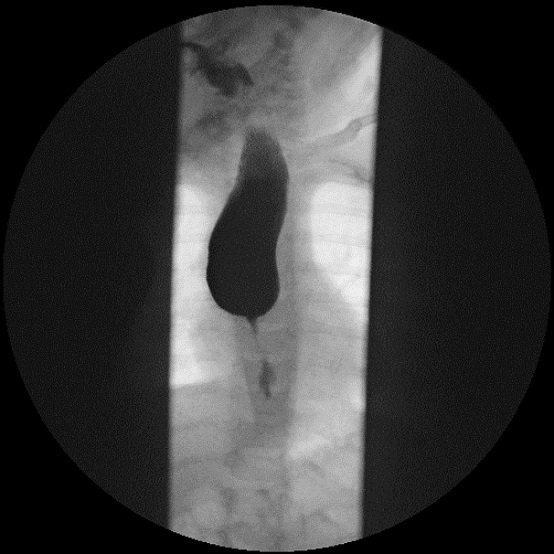

Como parte del estudio se realiza un estudio analítico y una ecografía abdominal, que no muestran alteraciones. Dada la persistencia del cuadro de vómitos, se decide realizar una endoscopia digestiva alta ( Fig. 1) en la que se evidencia una estenosis esofágica que impide el paso del endoscopio. El tercio proximal del esófago se muestra dilatado, sin estrías ni anillos. Se completa estudio con tránsito digestivo superior ( Fig. 2), donde se confirma estenosis esofágica en el tercio medio-distal, con escaso paso del contraste. En la anatomía patológica de la mucosa se observan cambios inflamatorios de características inespecíficas, sin metaplasia intestinal.

El esofagograma con contraste es la maniobra diagnóstica inicial, junto con la radiografía de tórax anteroposterior y lateral 3. Generalmente muestra una dilatación proximal seguida de un área corta de estrechamiento concéntrico aperistáltico, con imposibilidad para el paso del contraste.